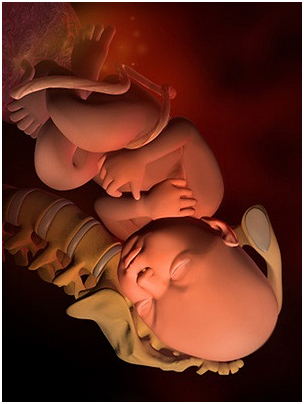

胎儿子宫位置示意图孕2个月 孕3个月 孕4个月 孕5个月 孕6个月 孕7个月...

胎儿子宫位置示意图孕2个月 孕3个月 孕4个月 孕5个月 孕6个月 孕7个月... -

怀孕第28周胎儿图 从现在开始,你就进入了孕晚期,要注意的事情很多呦!你要每天做胎动...

怀孕第28周胎儿图 从现在开始,你就进入了孕晚期,要注意的事情很多呦!你要每天做胎动... -